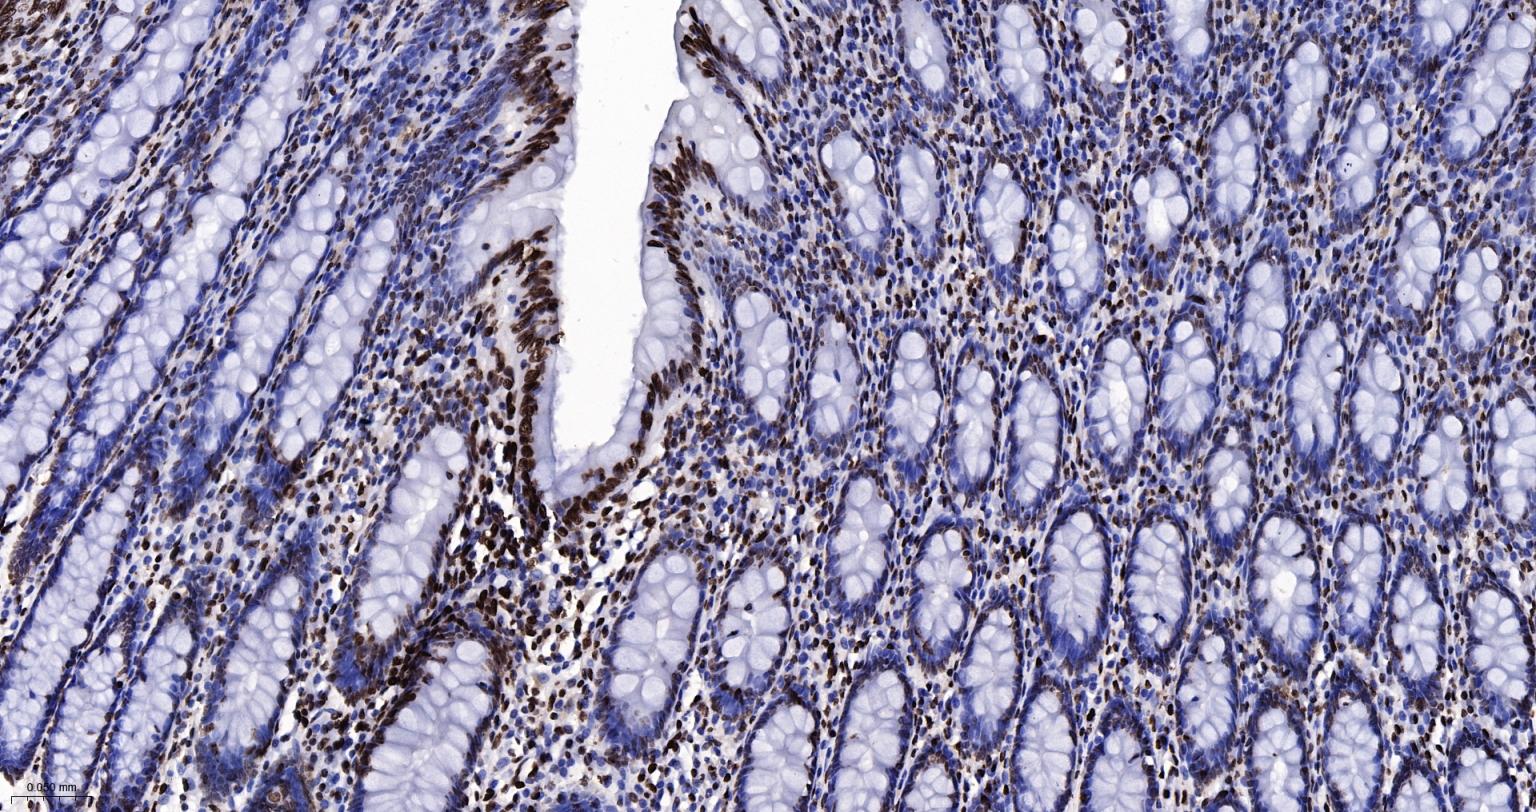

Paraformaldehyde-fixed, paraffin embedded Human Colon; Antigen retrieval by boiling in sodium citrate buffer (pH6.0) for 15 min; Antibody incubation with Histone H2A.X Monoclonal Antibody, Unconjugated(bsm-61080R) at 1:200 overnight at 4°C, followed by conjugation to the SP Kit(Rabbit, SP-0023) and DAB (C-0010) staining.

Paraformaldehyde-fixed, paraffin embedded Mouse Colon; Antigen retrieval by boiling in sodium citrate buffer (pH6.0) for 15 min; Antibody incubation with Histone H2A.X Monoclonal Antibody, Unconjugated(bsm-61080R) at 1:200 overnight at 4°C, followed by conjugation to the SP Kit(Rabbit, SP-0023) and DAB (C-0010) staining.

Paraformaldehyde-fixed, paraffin embedded Rat Colon; Antigen retrieval by boiling in sodium citrate buffer (pH6.0) for 15 min; Antibody incubation with Histone H2A.X Monoclonal Antibody, Unconjugated(bsm-61080R) at 1:200 overnight at 4°C, followed by conjugation to the SP Kit(Rabbit, SP-0023) and DAB (C-0010) staining.